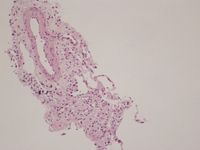

Avaliação histológica de uma amostra de biópsia pulmonar, revelando a presença de um infiltrado inflamatório, composto predominantemente por eosinófilos encontrados dentro do lúmen vascular e da parede vascular

BMJ Case Reports 2009; doi:10.1136/bcr.04.2009.1731. Copyright © 2011 by the BMJ Publishing Group Ltd